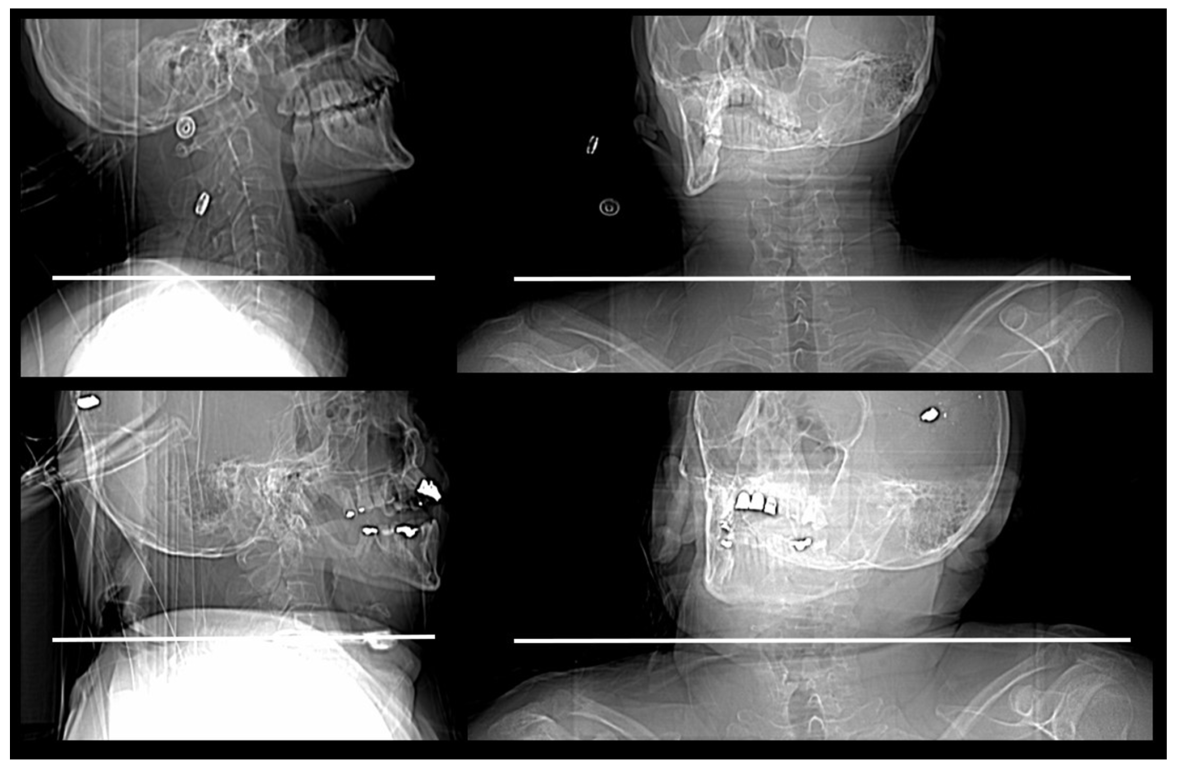

2.2. Human Cadaver Study

3.1. Cadaver Study